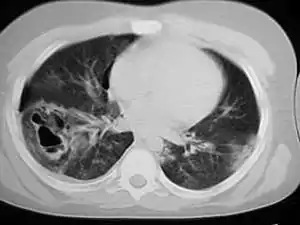

This CT scan, taken 22 days after pulmonary contusion with major chest trauma, shows that the contusion has completely resolved.[64]

Pulmonary contusion usually resolves itself[23] without causing permanent complications;[1] however it may also have long-term ill effects on respiratory function.[38][65] Most contusions resolve in five to seven days after the injury.[1] Signs detectable by radiography are usually gone within 10 days after the injury—when they are not, other conditions, such as pneumonia, are the likely cause.[27] Chronic lung disease correlates with the size of the contusion and can interfere with an individual's ability to return to work.[24] Fibrosis of the lungs can occur, resulting in dyspnea (shortness of breath), low blood oxygenation, and reduced functional residual capacity for as long as six years after the injury.[38] As late as four years post-injury, decreased functional residual capacity has been found in most pulmonary contusion patients studied.[43] During the six months after pulmonary contusion, up to 90% of people suffer difficulty breathing.[27][43] In some cases, dyspnea persists for an indefinite period.[7] Contusion can also permanently reduce the compliance of the lungs.[66]